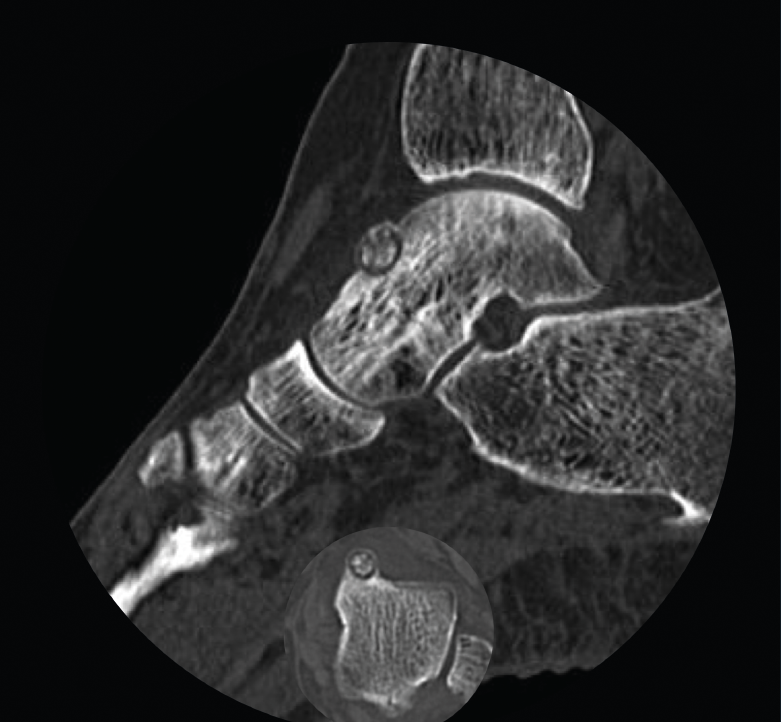

Figura 1. Tomografía axial computarizada inicial donde se observa una lesión yuxtacortical en el astrágalo de 8 mm de diámetro.

Se trata de una mujer de 64 años que presenta dolor en el tobillo izquierdo de 36 meses de evolución; la paciente refiere un dolor nocturno para el que precisa toma de salicilatos. Se realizó una radiografía que no evidenció lesiones óseas, la TAC nos informa de una lesión lítica yuxtacortical en el astrágalo de 8 mm de diámetro con calcificaciones de aspecto condroide en el centro de la misma (Figura 1). La RMN sugería un OO, ya que presentaba una tumoración ósea en el cuello del astrágalo con cambios inflamatorios periféricos y abundante edema óseo difuso del astrágalo (Figura 2).